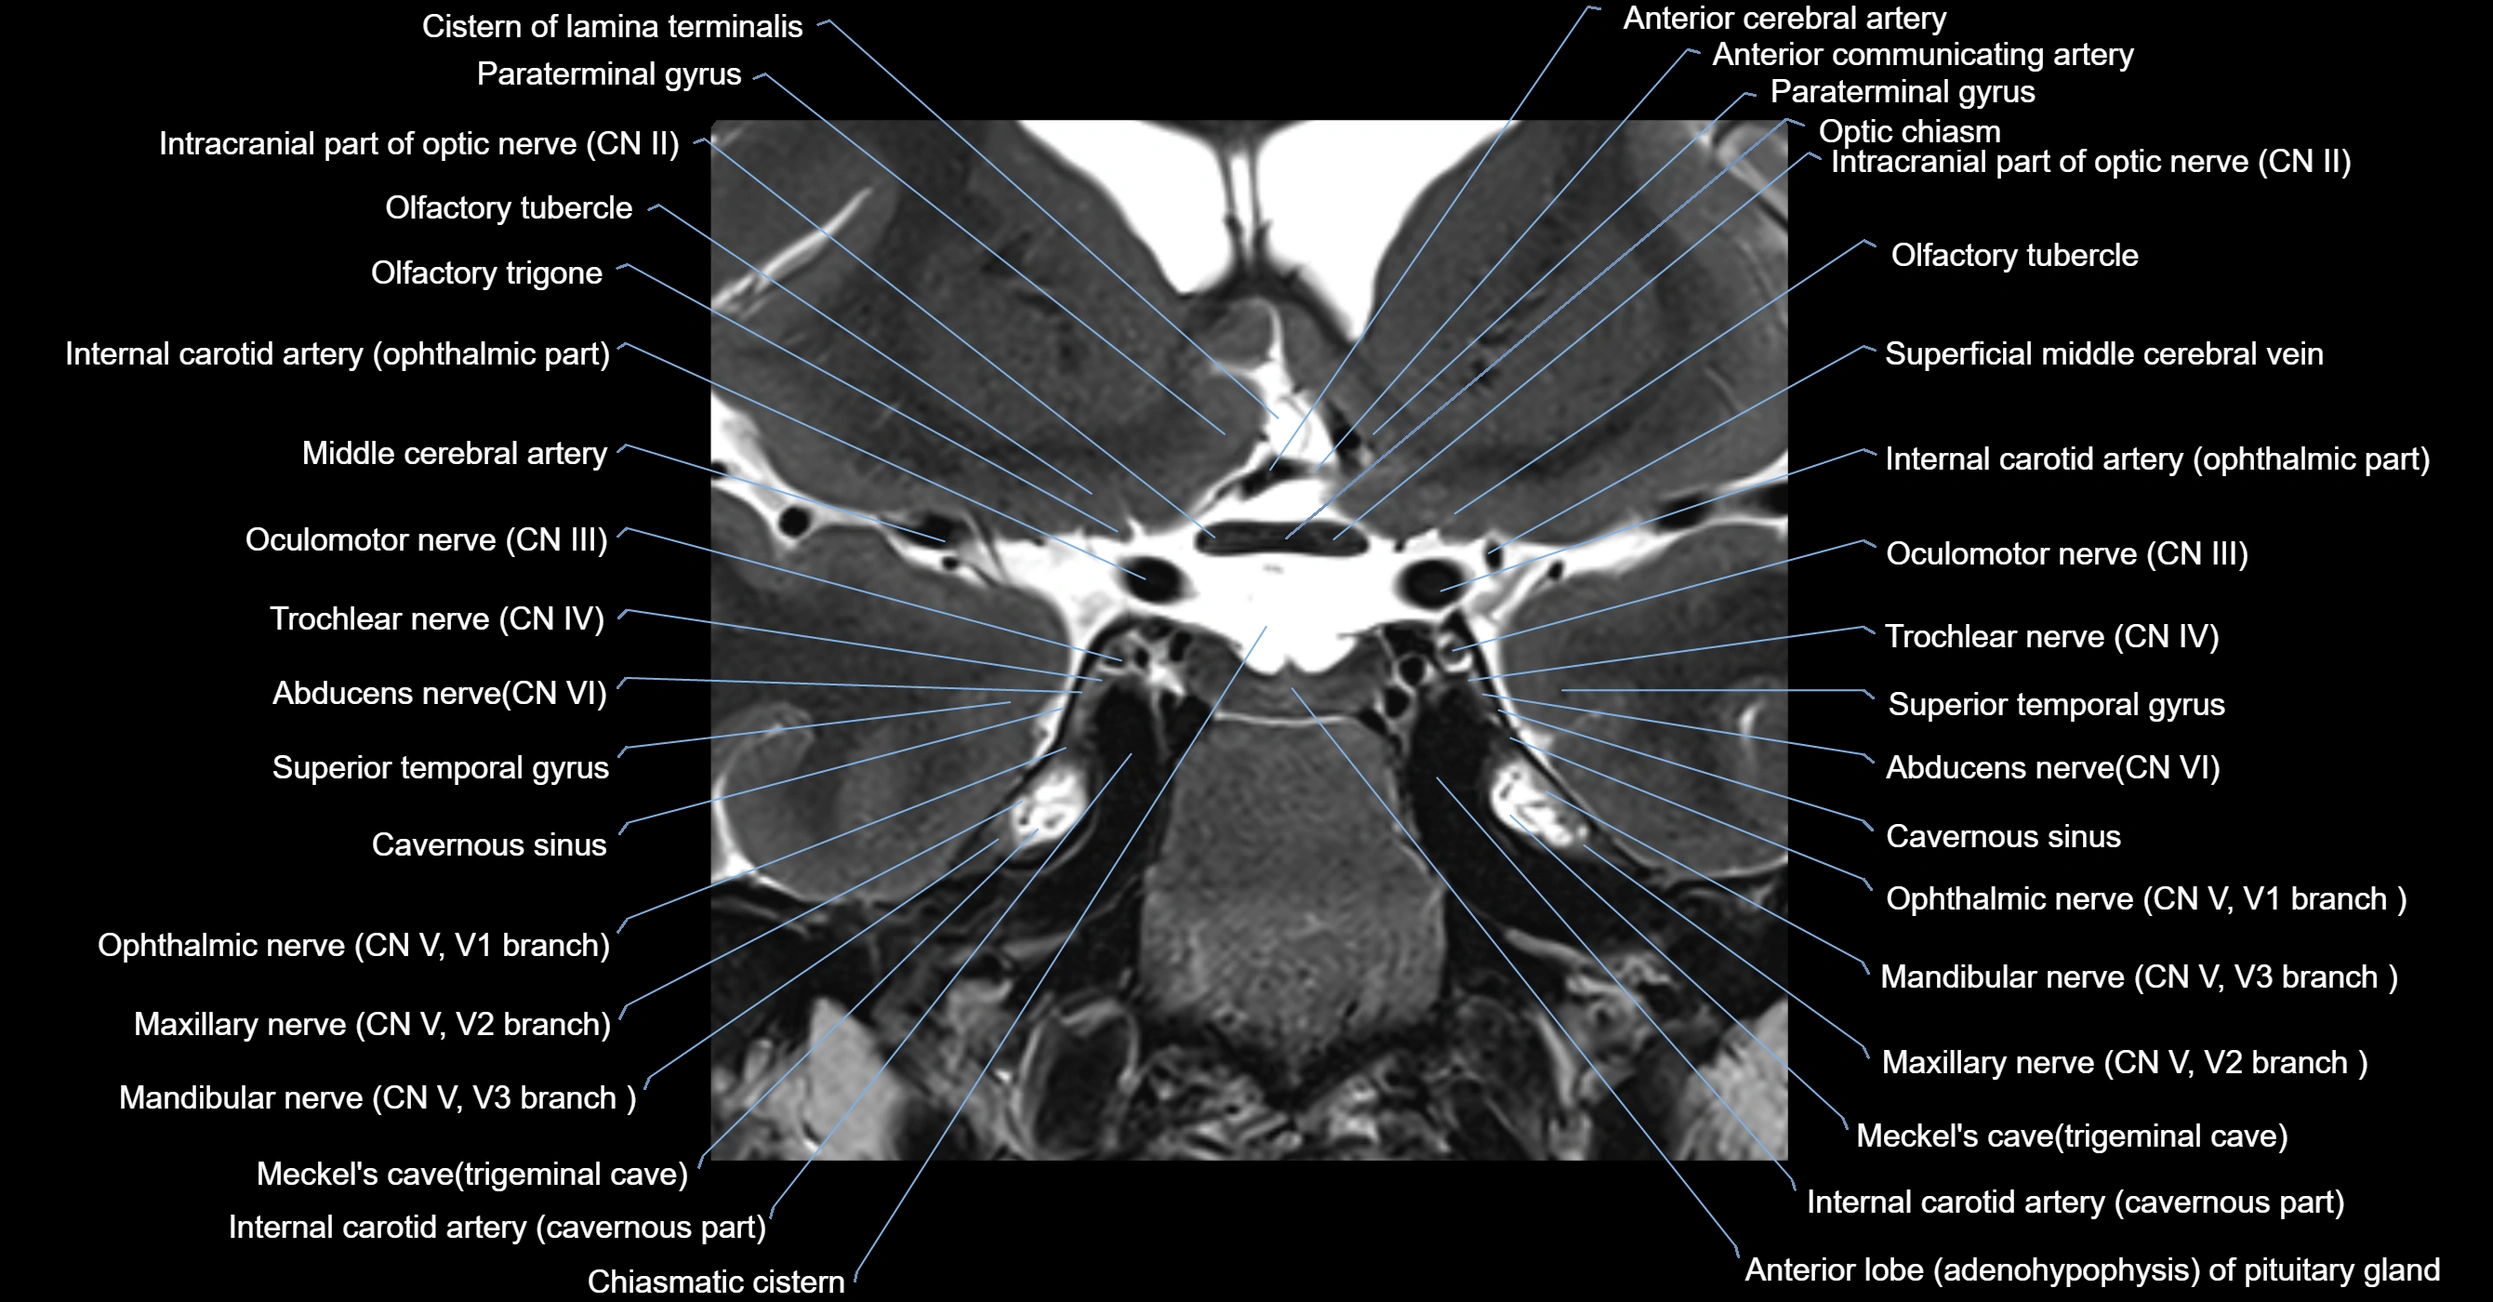

MRI Appearance

The abducens nerve is a small, thin, linear structure

Best visualized on high-resolution T2-weighted 3D MRI sequences (e.g., FIESTA or CISS)

Seen as a hypointense (dark) line running from the brainstem at the pontomedullary junction, traversing the prepontine cistern, and entering Dorello’s canal under the petrosphenoidal ligament, then into the cavernous sinus, and finally the orbit

May be challenging to visualize in standard MRI due to its small size

Pathology may be inferred by absence, displacement, or enhancement of the nerve

MRI images